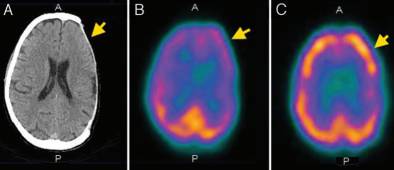

结果显示,颅骨成形术前,9例(26.5%)患者的GOS评分为5分,25例(73.5%)GOS评分为4分;颅骨成形术后,34例(100%)患者GOS评分为5分,较术前提高。各项认知测试结果表明,35.3%-90.9%的患者于颅骨成形术后认知功能改善(表1)。此外,94%患者的脑SPECT成像结果提示,在不同脑叶中脑灌注情况均得到改善(图1-4)。

图2. A.颅脑CT显示左侧颅骨缺损;B.颅脑SPECT示术前左额叶、顶叶和枕叶的脑血流灌注降低;C.颅脑SPECT示术后脑血流灌注较术前改善。